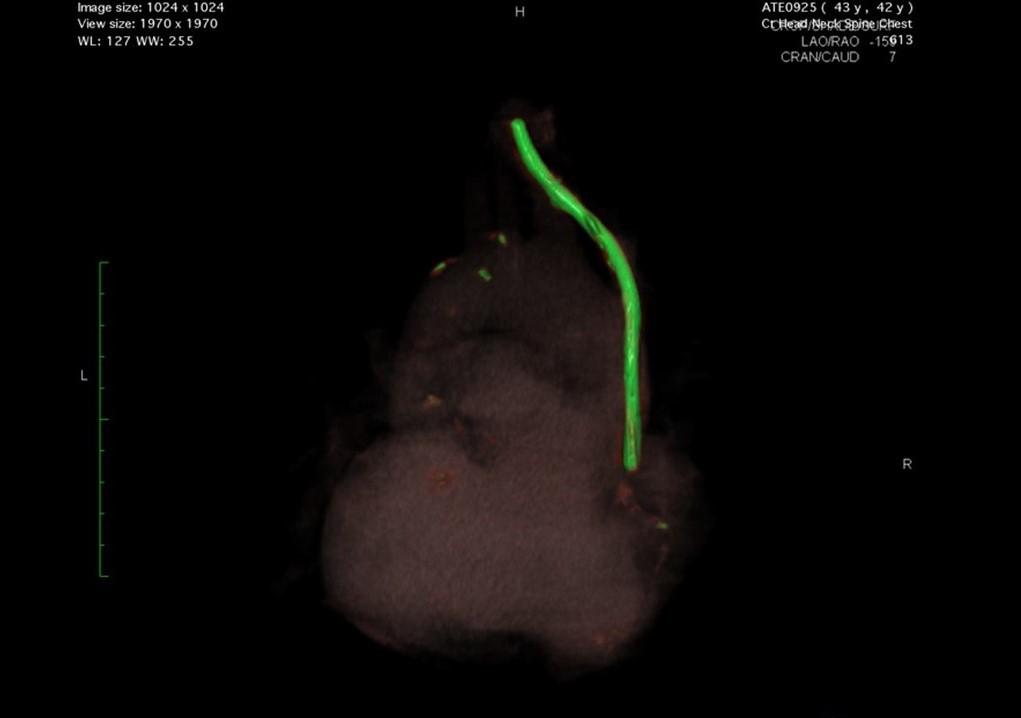

Main image

We are hopeful of finding a surgeon in Melbourne that can apply the same laser sheath removal technique. Going to the US currently is not feasible due to rising costs of surgery and the exchange rate both being cost prohibitive. The average cardiothoracic procedure in Australia is around $70,000 (for an extraction of pacemaker leads), so we are hopeful a surgeon can apply the same principal with an embedded fractured catheter. The major hurdle is the length of time the catheter has remained in situ and the fact they don't do these procedures routinely as it should never happen, hence being in this unique situation. The only way of getting to the US now will be if ACC change their legislation to enable treatment injury cases to get the surgery they need if it's not available in NZ. Thankyou so much to everyone who has donated, we can't reiterate enough how appreciative we are. The attached image is a 3D image created by the surgeon from the US showing the catheter and fragments in bright green sitting in the SVC (superior vena cava) inside the heart.